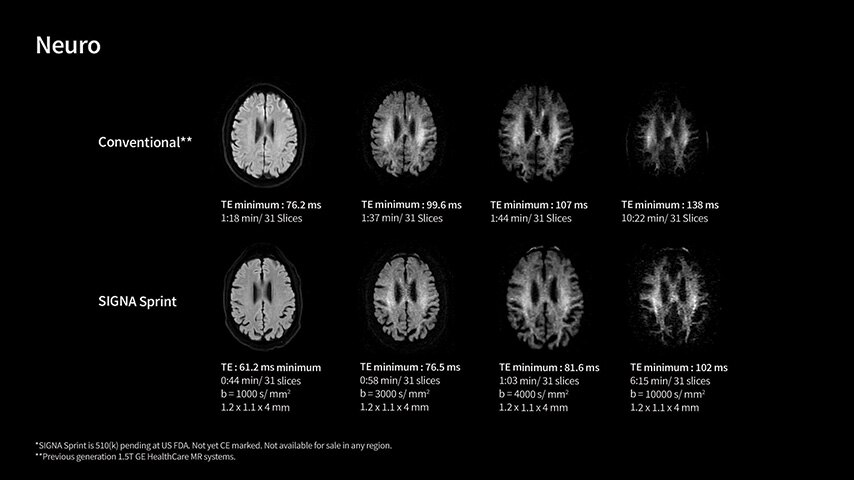

In oncological assessments, diffusion imaging is a critical clinical indicator. SIGNA Sprint offers clearer diffusion, reduced distortion, and improved SNR.¹

With GE HealthCare's comprehensive suite of deep-learning solutions integrated into SIGNA Sprint, you can unlock the full potential of your MRI system. No need for complicated patient setups or imaging protocols. The exceptional intelligence of our AI solutions offer multiple benefits, with AIR Recon DL giving pin-sharp images, Sonic DL accelerating scans up to 12x, and AIR x enabling automated slice placement. All helping to enhance your department’s workflow efficiency, increase patient throughput, and get the diagnostic clarity you need, faster.¹ Meaning you can spend more time on what truly matters—personalized patient care, enabling optimized treatment plans and treatment response monitoring—ultimately, supporting better clinical outcomes.